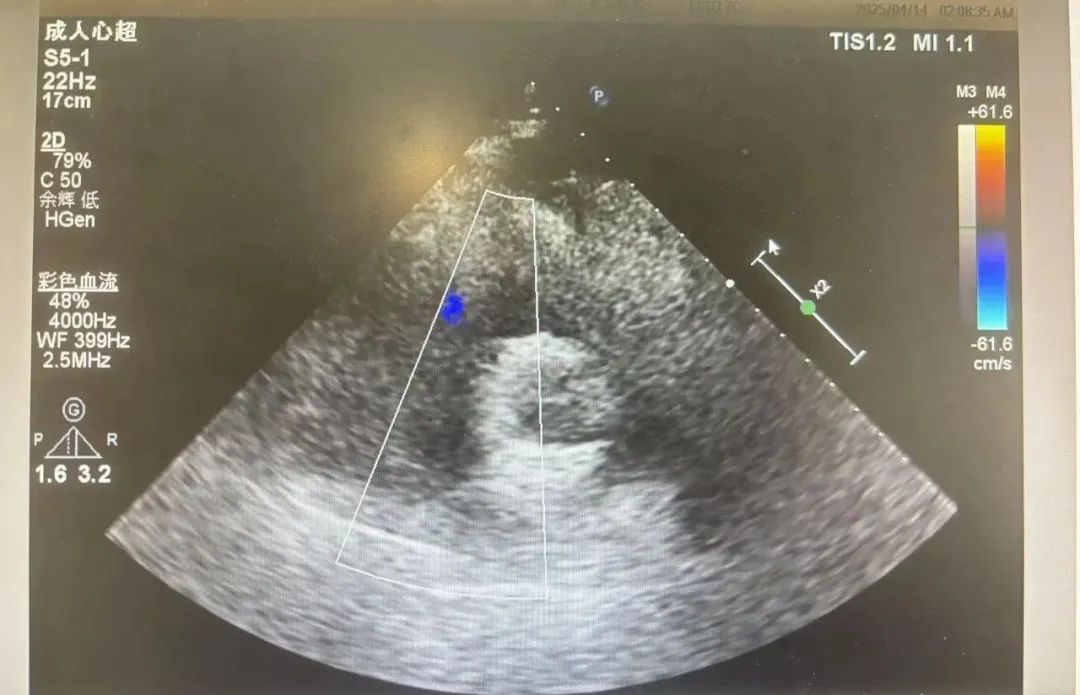

正常心脏如同精密的“四居室”,房间隔、室间隔和各组瓣膜分工明确,心外科学科带头人、主任医师张秀辉接诊后,为赵女士完善心脏彩超发现患者的心脏存在多处致命缺陷:

完全型心内膜垫缺损:心脏中央的“隔墙”完全缺失,左、右心房心室“互通”,血流紊乱加重心脏负担;

二尖瓣关闭不全:心脏的“单向阀门”无法闭合,血液倒流导致心脏扩大;

肺静脉异位引流:本应回流至左心房的左上肺静脉却回流到无名静脉,再流入到右心房。

眼前复杂的病变正如术前预估的那般棘手,张秀辉主任凭借丰富的经验和精湛的技术,小心翼翼地将薄如蝉翼的左上肺静脉重新连接到左心房,让肺静脉血回归正轨,恢复正常的心肺循环通路。历经3小时的精细操作,手术团队成功闭合心脏缺损、修复瓣膜功能。术后超声显示:房室间隔分流消失,瓣膜开闭良好,血流动力学显著改善!